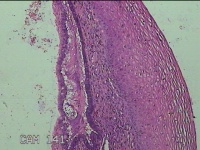

宫颈6点外缘、9点组织

性别

女

年龄

18岁

临床诊断

宫颈炎性疾病

一般病史

宫颈高危HPV感染

标本名称

大体所见

1.“宫颈6点外缘组织”:灰白粉红色不规则组织0.7x0.5x0.3cm两块。 2.“宫颈9点组织”:灰白粉红色不规则组织0.5x0.3x0.2cm一块。

良性病变。